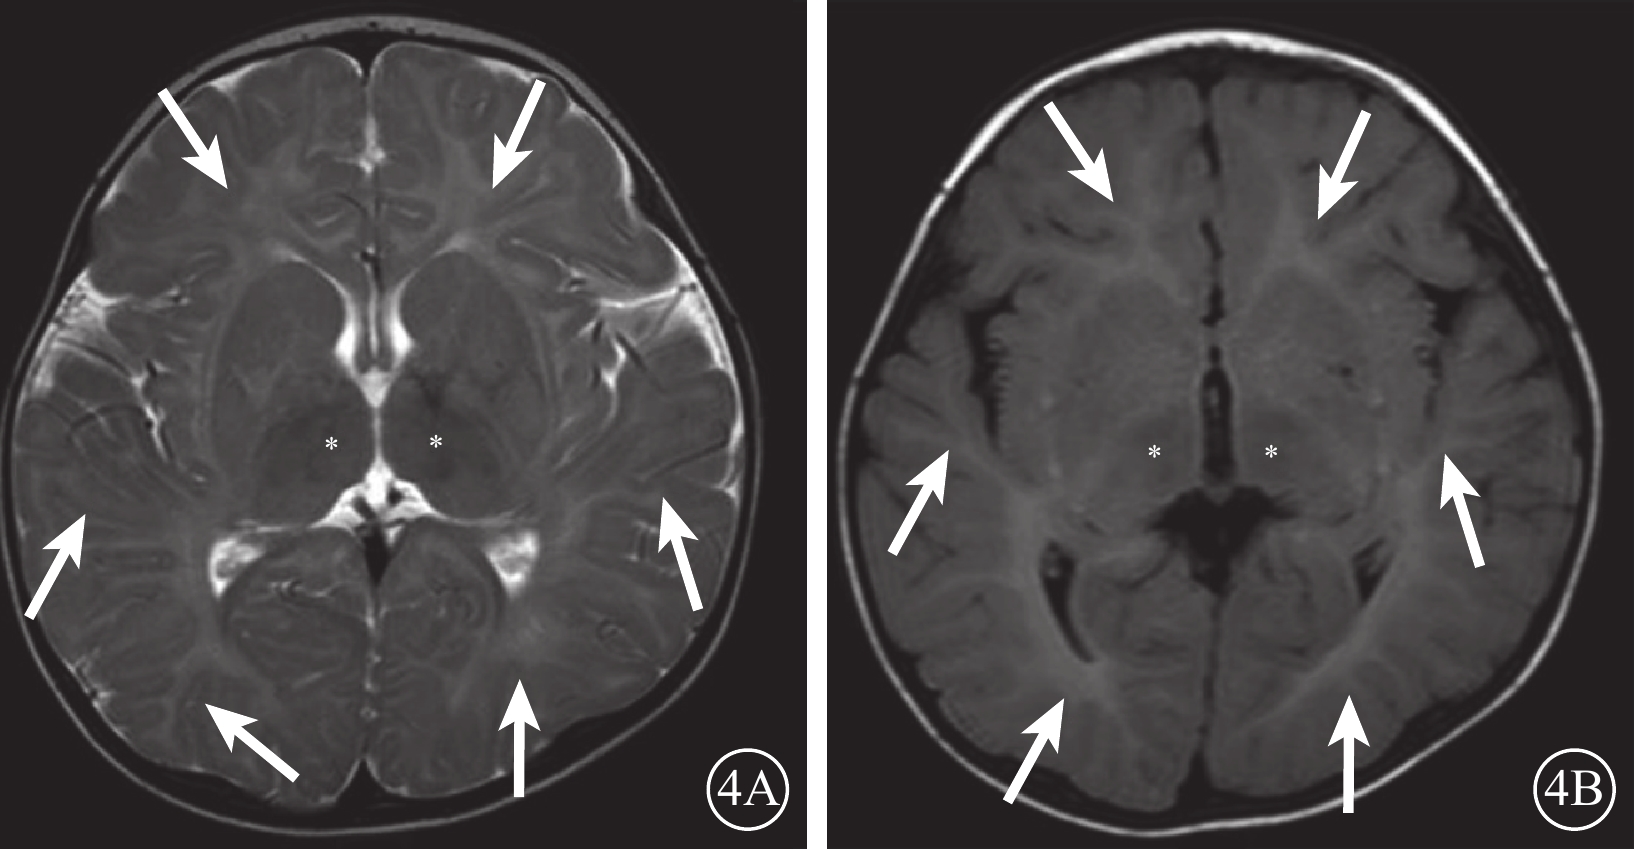

例3 患兒男,12個月。因出生7個月發育倒退,雙眼不能追視就診。足月出生。出生后7個月發育倒退,聲音刺激易“驚跳”;否認家族遺傳病史。眼部檢查:雙眼不能追視;眼球運動正常;其余眼前節檢查未見異常。眼底未見明顯異常。神經系統檢查:獨坐不穩;四肢肌張力高,雙側跟膝腱反射亢進。顱腦MRI檢查,雙側額、頂、枕及顳葉腦白質長T2信號,丘腦短T2信號(圖4)。實驗室檢查,外周血β-半乳糖苷酶活性1.6 nmol/(g·min)[正常值:144.7~350.4 nmol/(g·min)]。高通量全基因組測序結果:GLB1基因chr3:33058242 exon14 c.1438A>G(p.M480V)雜合突變(來源于母親)、chr3:33059944 exon13 c.1343A>T(p.D448V)雜合突變(來源于父親)(圖5)。診斷:L-iGM1。